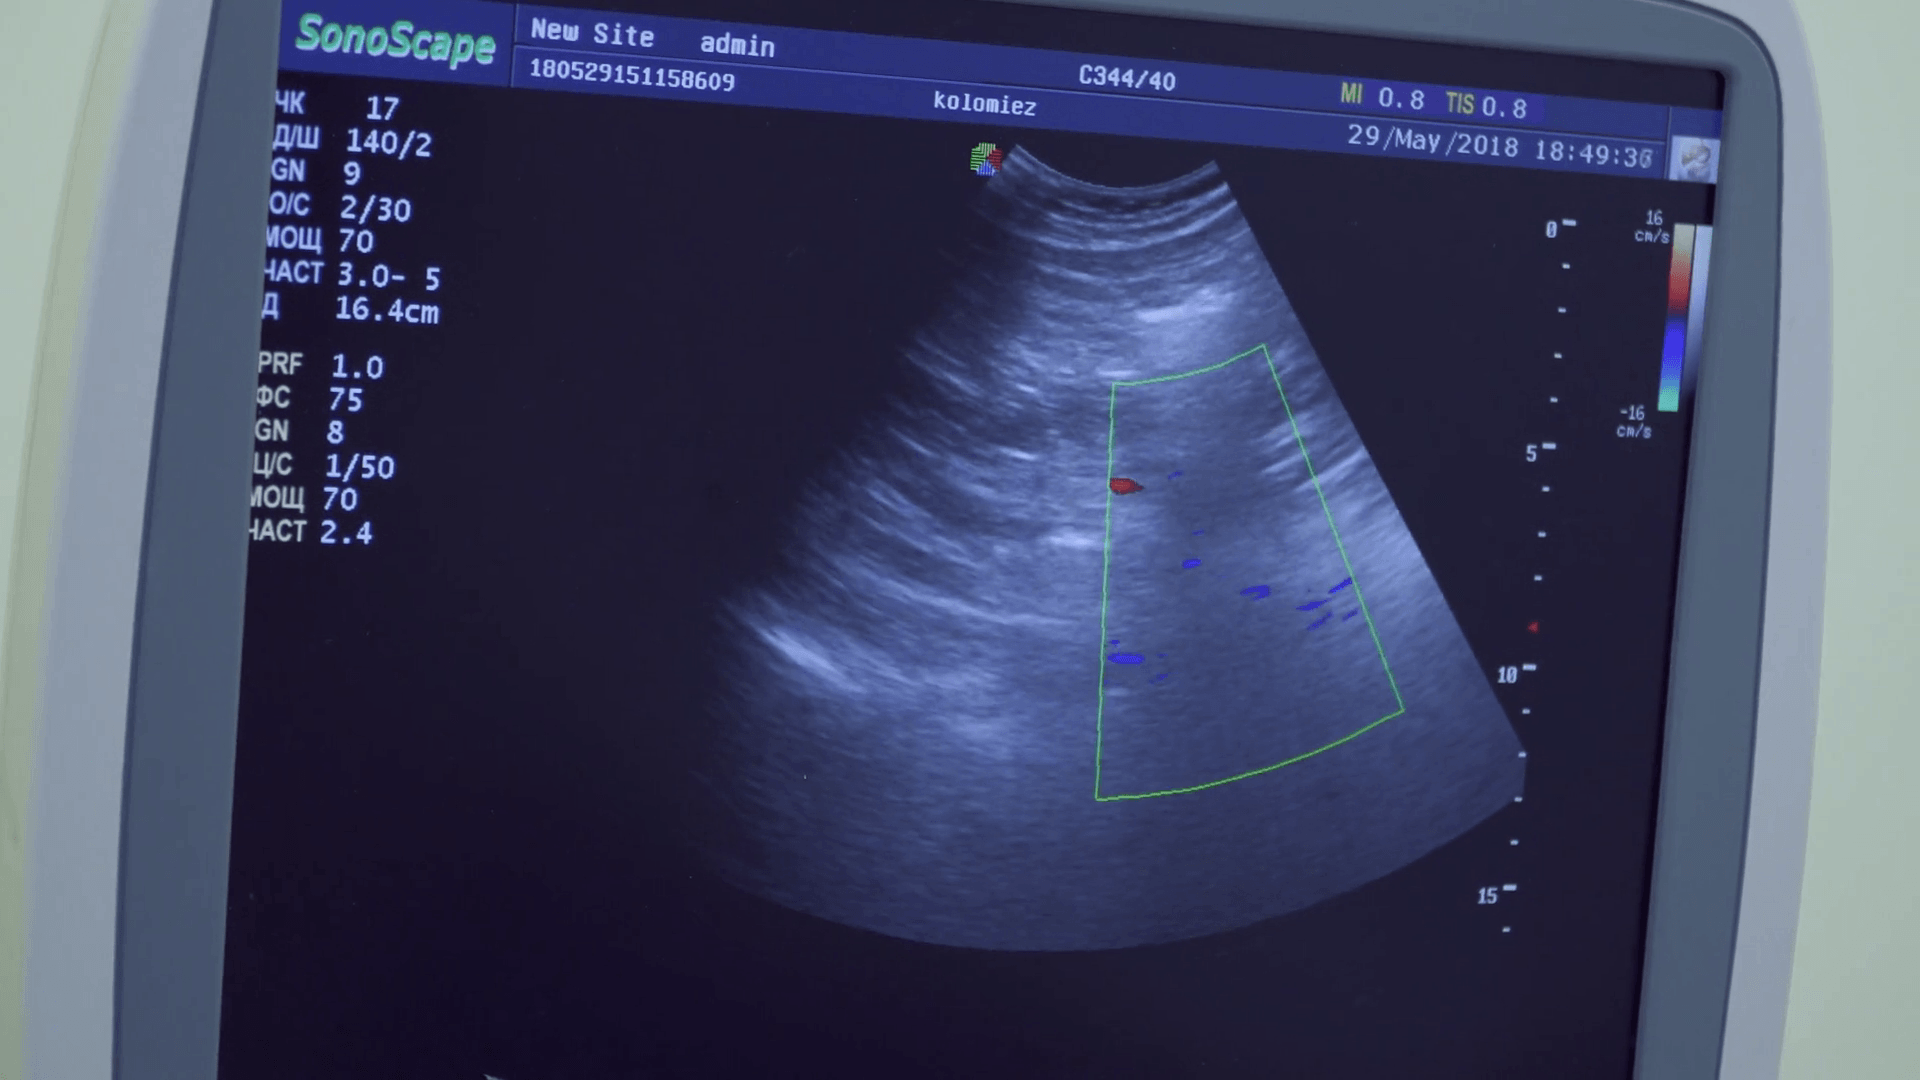

Colourful Image Of Modern Ultrasound Monitor Stock Photo - Image Of

www.dreamstime.comultrasound

www.dreamstime.comultrasound

Colourful Image Modern Ultrasound Monitor Ultrasonography Stock Photo

www.shutterstock.comUltrasound Wallpapers - Top Free Ultrasound Backgrounds - WallpaperAccess

www.shutterstock.comUltrasound Wallpapers - Top Free Ultrasound Backgrounds - WallpaperAccess